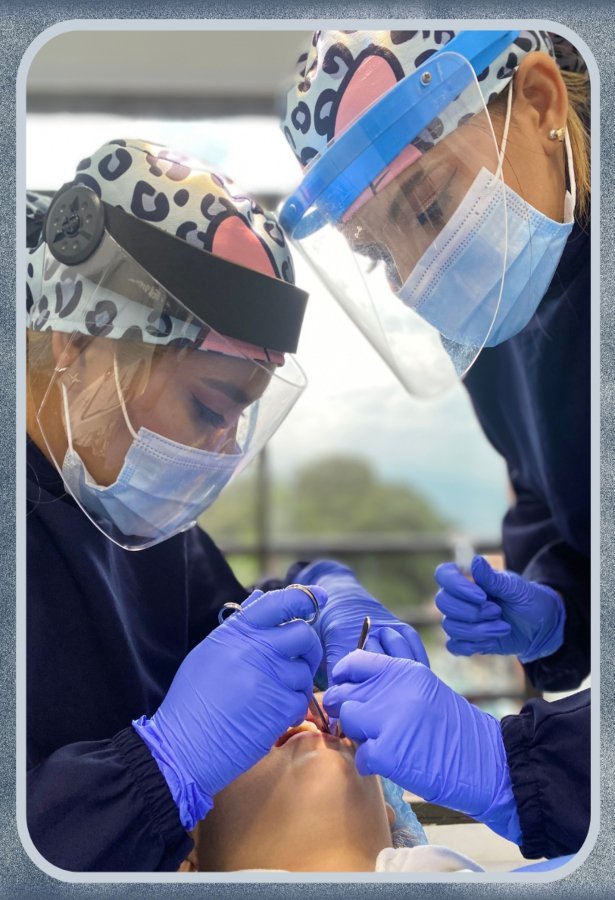

La cirugía oral es una rama de la odontología que se centra en el diagnóstico y el tratamiento quirúrgico de una variedad de problemas y afecciones relacionadas con la boca, lo...